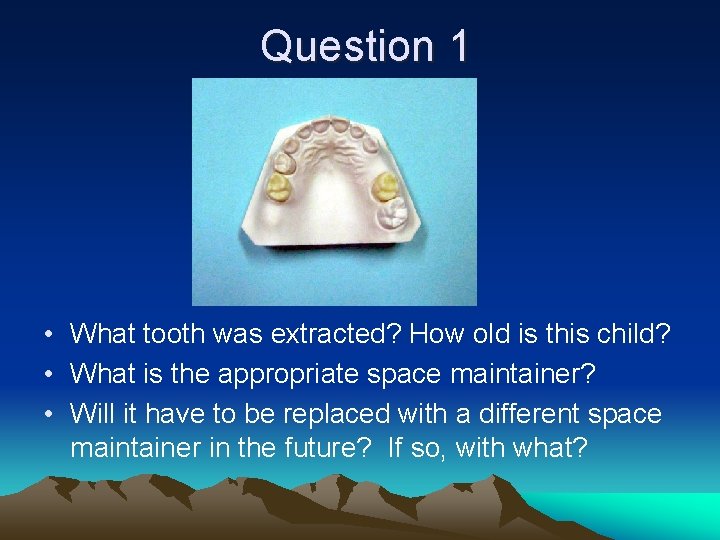

Question 1 • What tooth was extracted? How old is this child? • What is the appropriate space maintainer? • Will it have to be replaced with a different space maintainer in the future? If so, with what?

Question 1 • 5 or 6 y. o. child. Tooth #I extracted.

Question 1 • Band/Crown and Loop #J-H • Will not need replacement. #12 should erupt before #H or J exfoliate